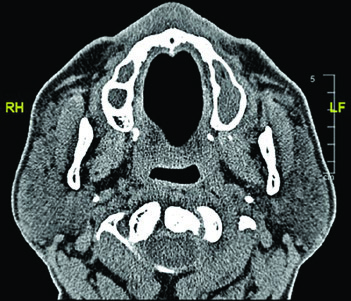

The figure demonstrates a case of high-grade mucoepidermoid carcinoma cT1N1M0 of the right submandibular gland. The CTV60–66 (red) covers the surgical bed while the CTV50–54 (green) encompasses ipsilateral nodal stations and the parapharyngeal space up to the skull base. This ensures adequate coverage even in early-stage but high-grade tumors.

A few additional clinical considerations merit attention when planning submandibular cases. The submandibular gland sits in a complex anatomical neighborhood — the mylohyoid muscle separates its superficial and deep lobes, the facial artery courses through or around the gland, and the marginal mandibular branch of the facial nerve runs superficially. During postoperative planning, the skin flap raised during surgery may thin the tissue between the treatment volume and the surface, potentially requiring bolus even in the absence of dermal invasion. Careful review of the operative note helps identify which structures were sacrificed, which were spared, and where the closest margin lies.